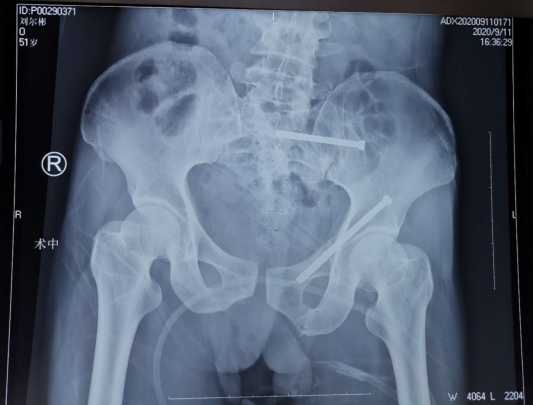

患者51岁,从5米高处坠落,腰臀部疼痛,活动受限,CT显示骨盆多发骨折,任海东主任和手术团队经过讨论,决定给患者进行骨盆骨折机器人导航下复位空心螺钉内固定手术。

术中,任海东主任通过机器人机械臂的精确运动,以及精准定位,规划螺钉方向及长度,避开髋臼缘及盆腔,拧入100mm空心钉固定左侧耻骨上支;再复位骶髂关节,准确地将一枚长度70mm空心螺钉置入,顺利完成骨盆骨折内固定微创手术。此术式对髋臼骨折来说,创伤如此微小——手术切口约1cm、出血量仅50ml,令人惊叹。

创伤骨科任海东主任说,骨科机器人手术中机械臂的精准度超过人手,解决了骨科手术“看不见、打不准、拿不稳”三大难题,让骨科手术更完美。若是采用传统手术方法,只能进行敞开式手术,手术切口要长达10厘米以上,并且由于缺少可视化设备,要反复地透视定位,手术的出血量达300-400ml,手术时间要2-3个小时才行,且精确性较低,后遗症多,病人康复时间也会因此延长。而如今,患者手术螺钉精确定位,伤口仅2个“小眼”,不但减少了痛苦,而且通过机器人手术还能减少机体应激反应,加速康复,大大缩短术后机体恢复的时间。